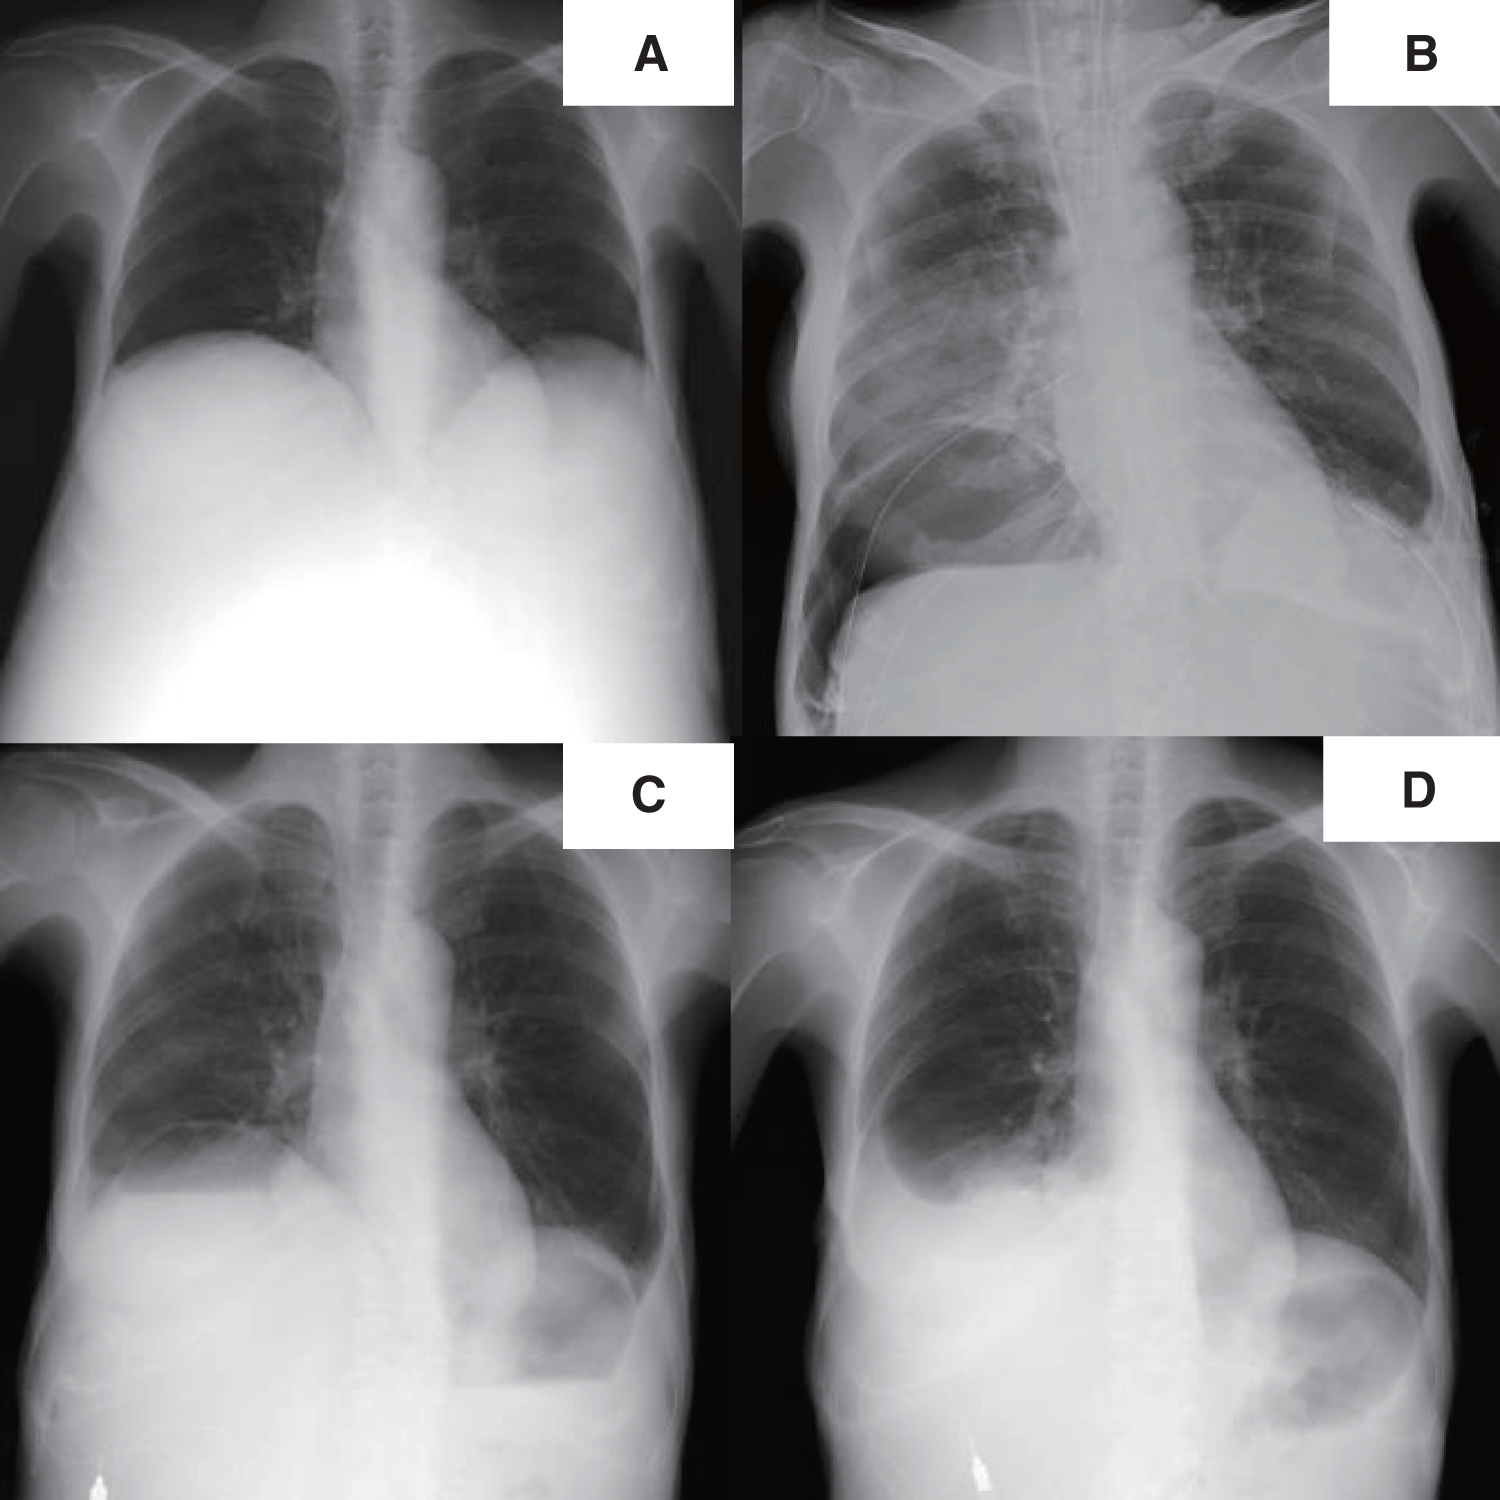

Fig. 1

X-ray imaging. Before liver transplantation, the right diaphragm was significantly elevated (A). From the first day after transplantation, a cystic shadow was observed in the right lower lung field (B), and an air–fluid level was observed within the cyst before the pneumatocele operation (C). There was no cystic shadow on the chest X-ray image at the time of discharge (D).

A chest radiograph revealed a round hypertranslucency with air–fluid levels on the right side since POD 1 (Fig. 1B and 1C), and no further evaluation was made at that time. However, because the hypertranslucency persisted, follow-up computed tomography (CT) was performed on POD 18, and revealed an air–fluid level above the diaphragm in the right thoracic cavity (Fig. 3A–3D). The patient was initially considered to have an intrathoracic hematoma, and thoracoscopic evacuation of the hematoma was planned.

Contrary to our initial expectation, thoracoscopic investigation revealed no intrathoracic hemorrhage; instead, there was a large cystic change inside the lung parenchyma, which was thought to be a pneumatocele that had formed at the basal area of the right lower lobe (Fig. 4A). Surgical resection was preferred given the risk of pneumatocele infection due to intra-cystic hematoma and immunosuppression for liver transplantation. Wedge resection was satisfactory to preserve as much remaining lung parenchyma as possible. From a different perspective, wedge resection was a better way to lower the risk of postoperative empyema, which is higher in lobectomy or segmentectomy. However, simple wedge resection was impractical considering the thickness of the lung parenchyma adjacent to the pneumatocele. It was thought that if the intra-cystic hematoma was evacuated, the thickness of the adjacent lung parenchyma would become thinner and would allow wedge resection with a stapling device. Therefore, the pneumatocele was incised, and the intra-cystic clot was removed to reduce its size (Fig. 4B and 4C). Wedge resection was subsequently performed using a stapling device. The staple line was reinforced with 4-0 polypropylene sutures, a polyglycolic acid sheet (Gunze, Osaka, Japan), and fibrin glue (KM Biologics, Tokyo, Japan) (Fig. 4D). The postoperative course of the patient was uneventful, and she was discharged 18days after resecting the pneumatocele (Fig. 1D).

The typical appearance of a pneumatocele on CT is a round thin-walled cavitary lesion with air–fluid levels.9,10) In our case, the CT findings were compatible with a pneumatocele (Figs. 3A–3D), but we could not make a correct preoperative diagnosis. This was largely driven by the incorrect assumption that liver surgery would not cause structural changes in the lung parenchyma unless there was direct injury. Additionally, a small hole in the diaphragm could be a source of unusual air retention in the thoracic cavity. Eventually, we considered that a pneumatocele had formed in our patient, triggered by the remarkable alleviation of the distended diaphragm.